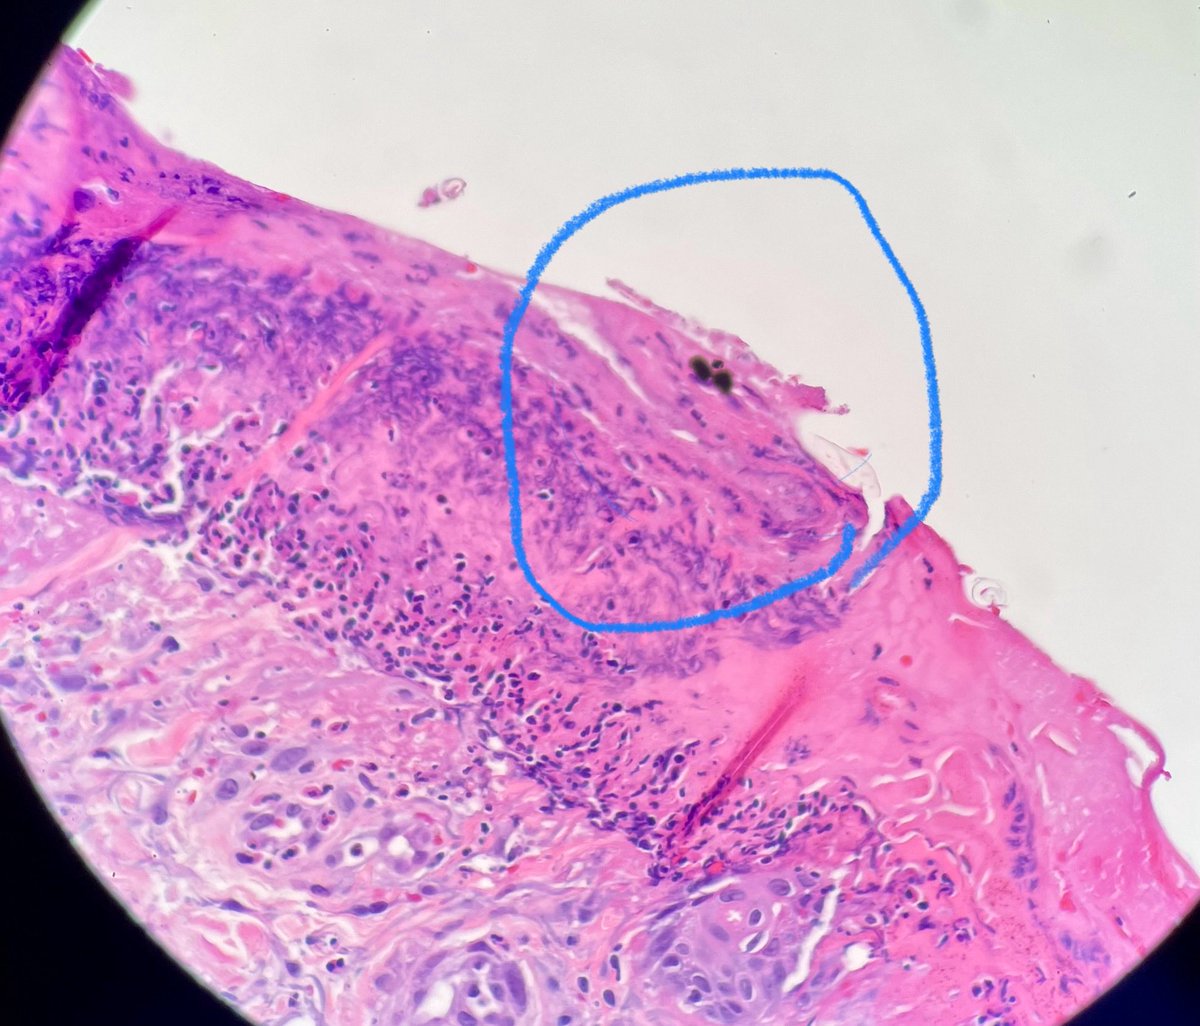

Silvija Gottesman MD Alejandro Gru (Ale) J Cutan Pathol Katy Veprauskas Maxwell Fung, MD Gregory A Hosler Henry YANG David Terrano Dermpath-L Dermpath_doc_trish Tristan Rutland MBBS FRCPA IFCAP Etan Marks, DO Maryam Aghighi, MD. DABP. Jerad Gardner, MD Cacey Peters, MD, FCAP, FASDP Pembe Oltulu, MD Walter Klein MD Andrea P Moy, MD Patrick Rush Jisun Cha MD FAAD Sara Shalin James A. Ramirez Joseph Susa, DO Rosalynn Nazarian MD 🅰🅼🆈🅷🅳🅴🅴🅺🅴🅽🅼🅳 Mariantonieta Tirado Vijay Shankar S Mike DeWall, D.O. Olaleke Folaranmi David Larson Luis Humberto Cruz C Kamran Mirza MD PhD - کامران مرزا Toño Navarro, M.D. 🔬🎗️ Nicole D. Riddle, MD, MSHI, FCAP (she/her) Haneen Salah Save the Date. Save the Date. Hot off the press. Next #dermpathJC to take place on 01/26/23 at 9pm EST, here on Twitter. Open access link at: jamanetwork.com/journals/jaman… #dermpath